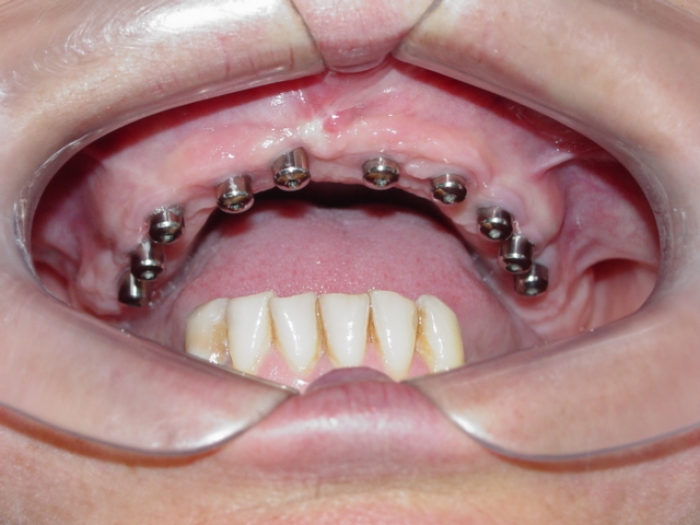

Implantes instalados com cicatrizadores

Prótese fixa em porcelana instalada sobre os implantes